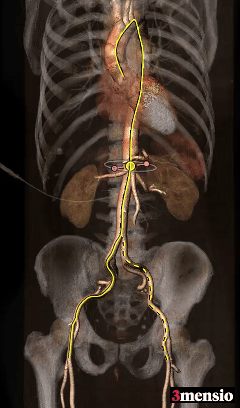

术前CT分析

患者为Type-1型二叶式主动脉瓣,无钙化

Type-1型二叶式主动脉瓣,R-L融合

主动脉弓部角度98°

外周入路条件尚可